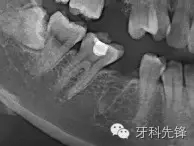

以下是也是一列健康牙拔除的病例。

拔牙斷根了怎么辦?

可以看到牙槽窩里面有一個(gè)斷根。